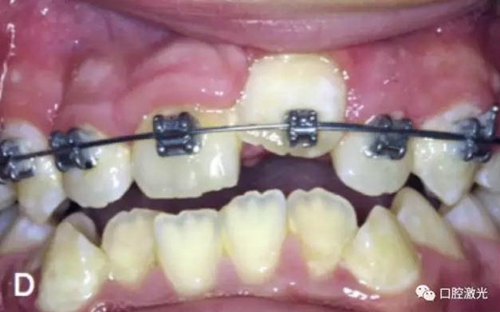

治療前

激光牙齦切割后即刻

粘接托槽

3周后效果